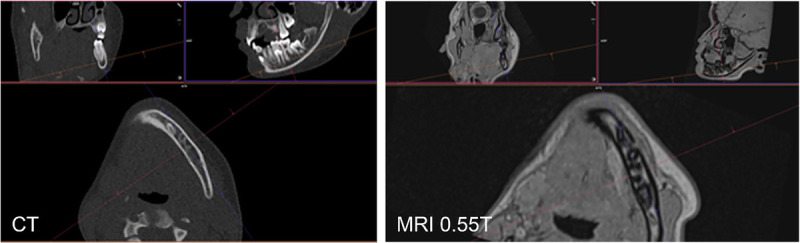

Objectives: This study sought to elucidate the diagnostic performance of 0.55 T magnetic resonance imaging (MRI) for pediatric dental imaging, specifically in terms of the image quality (IQ) for detecting ectopic and/or supernumerary teeth, compared with routine ultra-low-dose computed tomography (ULD-CT) of the jaw.

Materials and methods: A total of 16 pediatric patients (mean age: 12.4 ± 2.6 years, range: 9-17 years) with ectopic and/or supernumerary teeth screened from January 2023 to January 2024 were enrolled in this prospective, single-center study. All patients underwent ULD-CT as the clinical reference standard and 0.55 T MRI as the study scan on the same day. A 0.6-mm isotropic 3-dimensional T1w FLASH sequence was developed with a dedicated field of view of the upper and lower jaws. ULD-CT was performed using a new single-source computed tomography (CT) scanner equipped with a tin filter (Sn100, slice thickness: 1 mm, quality reference mAs: 24). The IQ for the tooth axis, the tooth length, the tooth root, root resorptions, cysts, the periodontal ligament space, and the mandibular canal was evaluated twice by 3 senior readers using a 5-point Likert scale (LS) (LS score of 1: insufficient, 3: reduced IQ but sufficient for clinical use, and 5: perfect) and compared between both methods. Subsequently, the results were dichotomized into nonvalid (LS score of ≤2) and valid (LS score of ≥3) for clinical use.

Results: A total of 49 ectopic and/or supernumerary teeth in 16 pediatric patients were investigated using ULD-CT (CTDI: 0.43 ± 0.09 mGy) and 0.55 T MRI. The mean MRI acquisition time was 9:45 minutes. Motion artifacts were nonsignificantly different between 0.55 T MRI and ULD-CT ( P = 0.126). The IQ for the tooth axis, the tooth root, root resorptions, and cysts was similar between the methods. The IQ for the periodontal ligament space and tooth length favored ULD-CT by 14% (confidence interval [CI]: 4.3%-24%) and 7.5% (CI: 1.8%-13%), respectively, whereas that for the mandibular canal favored 0.55 T MRI by -35% (CI: -54%-16%). Sufficient IQ was found especially for cystic lesions (CT: 100% sufficient, MRI: 95% sufficient), the tooth root (CT: 100%, MRI: 98%), root resorptions (CT: 94%; MRI: 85%), the tooth axis (CT: 100%; MRI: 98%), and the tooth length (CT: 99%; MRI: 91%).

Conclusions: The findings indicate that 0.55 T MRI is a feasible, radiation-free technique for delineating ectopic and/or supernumerary teeth in pediatric patients. Nevertheless, to date, 0.55 T MRI has not yet been able to provide an optimal IQ for all anatomical tooth and jaw structures. In cases of advanced clinical indications that require optimal spatial resolution, high-resolution CT or cone-beam CT may still be necessary.